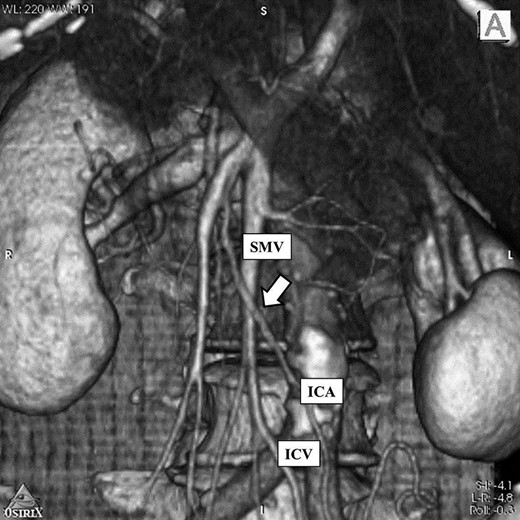

A 76-year-old woman known since early childhood to have situs inversus totalis was referred to the Breast Surgical Department for left breast cancer. She underwent F-fluorodeoxy-glucose positron emission tomography-computed tomography (FDG-PET/CT), because of high level of carcinoembryonic antigen (CEA). PET/CT image showed FDG uptake at the ascending colon (Fig. 1). Therefore, we were consulted by the doctor of Breast Surgical Department. The patient was admitted to our department for further evaluation and surgical treatment. And the treatment for the colon cancer preceded the treatment for breast cancer because of advanced stage of the colon cancer.

PET/CT image showed FDG uptake at the ascending colon (arrow).